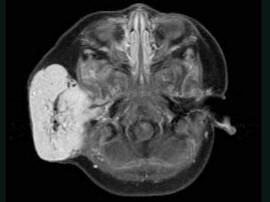

问题 老年患者,右侧面部肿胀,呈青紫色,MRI检查如图所示,请选择最可能的诊断 ( )

选项 A、神经纤维瘤 B、神经鞘瘤 C、囊肿 D、脓肿 E、血管瘤

答案 E